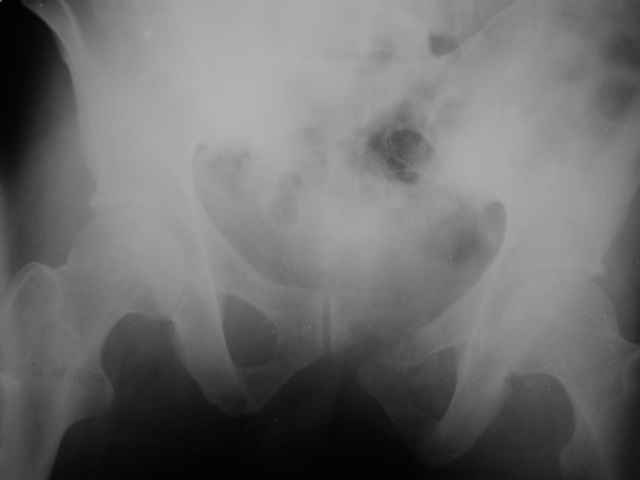

Можно посмотреть на нынешние снимки таза в аппарате, фас и inlet?

Отправитель: Владимир Бахарев 16 Ноябрь 2006, 12:13

Снимки вот